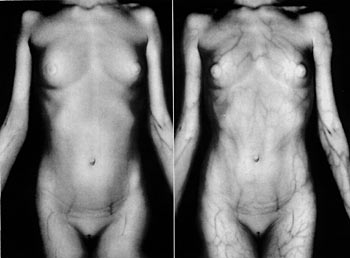

In 1961, Gibson published an interesting application of infrared in a paper entitled 'postprandial intensification of venous pattern' in Medical Radiography and Photography. In this presentation he demonstrated how the superficial venous pattern in a 12-year-old girl became greatly intensified following lunch. He suggested caution in interpreting venous patterns of the trunk and abdomen in view of this abnormal finding (Figure 22). Gibson presented this intriguing anomaly in the hope that other workers would attempt to use infrared to investigate other abnormalities in the vascular system.

Superficial venous pattern

Figure 22 (above). Intensification of superficial venous pattern following lunch.